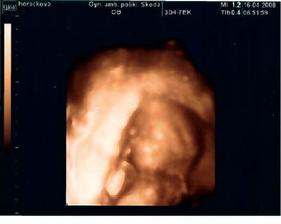

•••••••••• 16.4.2008 (19+5tt) výsledky z tripplů máme v pořádku, dostali jsme první 3D fotečku, jen nám paní doktorka nakonec nedělala screening ve 20tt, protože nám ho budou dělat v pondělí 21.4. v Praze (prý stačí jen jednou)